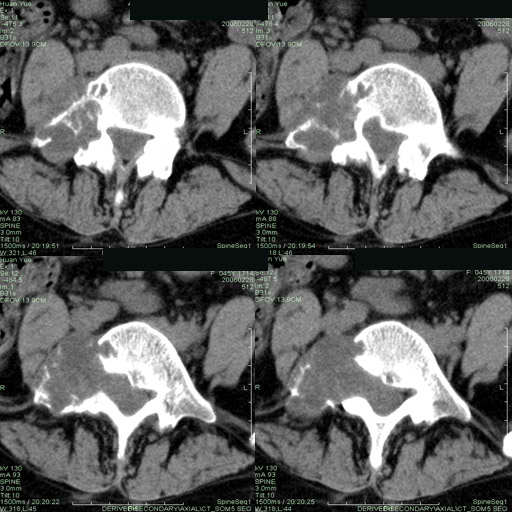

以下是引用听蝉观竹在2006-3-5 23:09:00的发言:[br]这个病例不考虑神经源性肿瘤,首先考虑转移瘤,因为它不是受压造成骨质吸收,而是从骨骼的松质部分由中心向外破坏的,不仅仅是横突,而且同侧椎弓根也破坏了。[br]神经源性肿瘤-----受压造成骨质吸收。[br]转移性肿瘤------从骨骼的松质部分由中心向外溶骨破坏,多见椎弓根也破坏。

以下是引用徐大夫在2006-3-5 20:32:00的发言:[br]骨缺损区边缘有硬化,结合部位,考虑神经源性良性肿瘤。